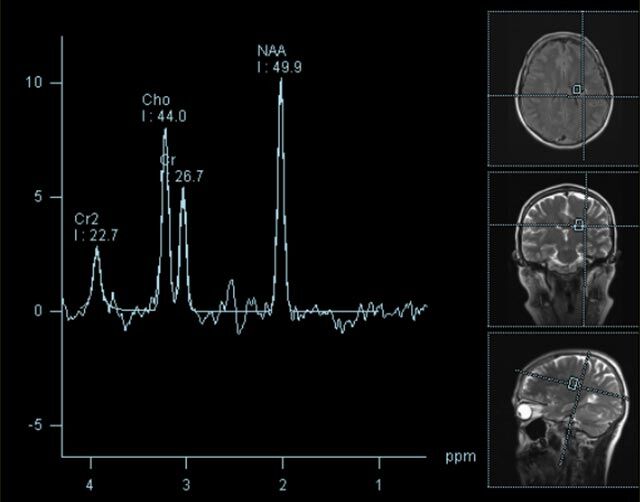

• MR-Spektroskopie

Diese Untersuchung führen wir ausschließlich an unserem Standort in Leipzig am Diakonissenkrankenhaus durch. Bitte nehmen Sie zur Vereinbarung eines Termins telefonischen Kontakt mit uns auf: 0341 3937-3000 oder schreiben Sie uns eine E-Mail an: